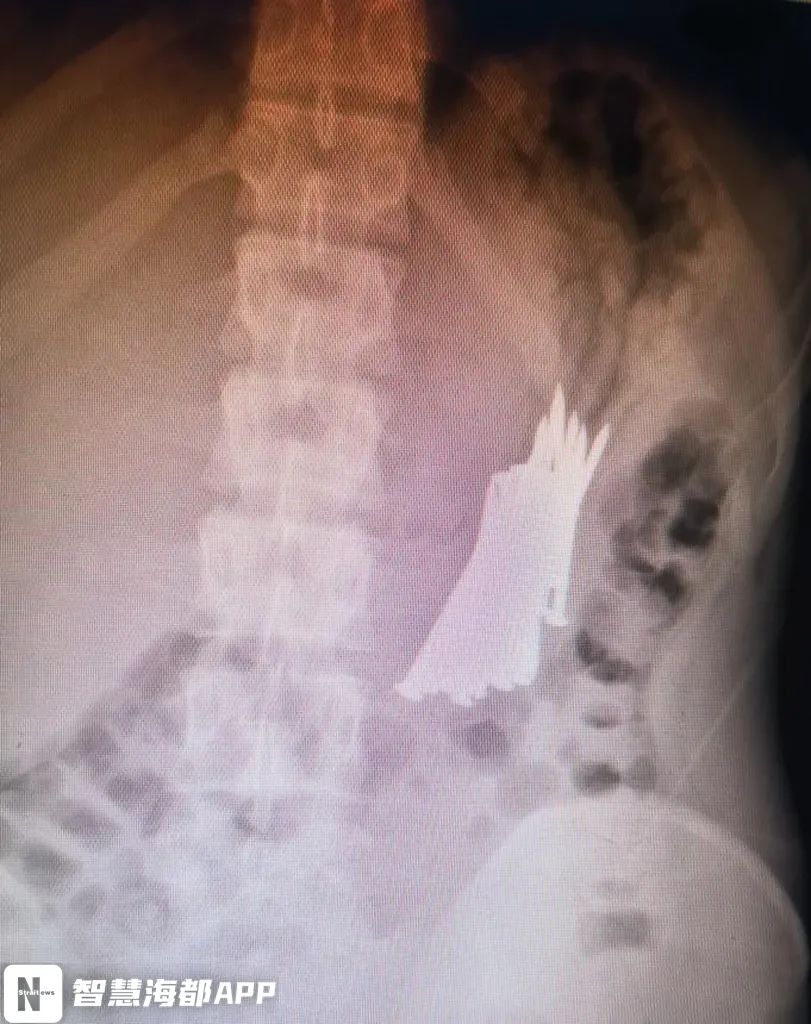

医生检查发现,丁丁胃内滞留大量钉子状物体,头端异常尖锐。“铁钉一旦滑入小肠,导致肠穿孔,进而就可危及生命,后果不堪设想!”医生说。

最终,医生们决定在内镜下,替丁丁取出钉子。当胃镜进入瞬间,密密麻麻的铁钉就出现在大家的眼前,画面触目惊心!经过3小时的手术,丁丁体内36根铁钉终于被全部取出。

每根钉子长约5.5cm

尾端十分锐利